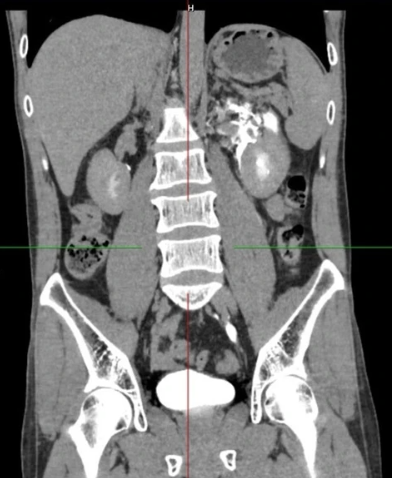

Vỡ bể thận niệu quản trái, thoát nước tiểu quanh thận trái. Ảnh: BVCC.

Kết quả siêu âm và CT-Scanner khẩn cấp cho thấy một viên sỏi kích thước khoảng 4 mm kẹt ở 1/3 dưới niệu quản trái, gây tắc nghẽn hoàn toàn dòng nước tiểu từ thận xuống bàng quang.

Theo bác sĩ Mai Văn Lực, khoa Phẫu thuật Thận Tiết niệu - Nam học, Bệnh viện E, dù thông thường sỏi nhỏ có thể được điều trị nội khoa để tống sỏi ra ngoài, nhưng trong trường hợp này, tắc nghẽn đột ngột khiến áp lực trong đài - bể thận tăng cao, dẫn đến vỡ bể thận - niệu quản. Nước tiểu thoát ra khoang sau phúc mạc, bao quanh thận trái với số lượng lớn, đe dọa nhiễm trùng huyết và suy thận cấp.